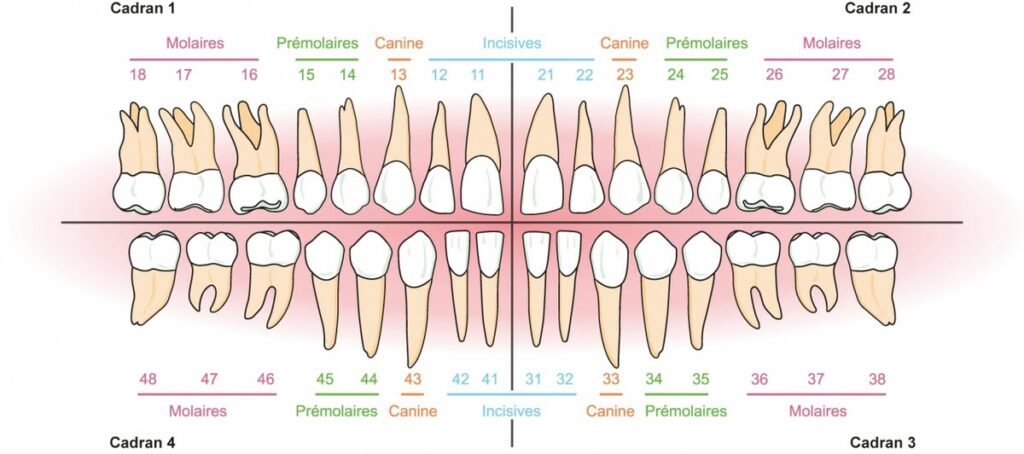

Comprendre l’Anatomie Endodontique : Les Bases Essentielles

La Cavité Endodontique : Un Espace aux Dimensions Critiques

La cavité endodontique est cet espace inextensible délimité par la dentine. Elle se divise en deux zones distinctes :

La chambre pulpaire : située dans la partie coronaire, elle est délimitée par le plafond pulpaire en haut et le plancher pulpaire en bas. C’est votre zone de travail principale lors de la création de la cavité d’accès.

Le canal radiculaire : s’étend du plancher pulpaire jusqu’au foramen apical. Il peut présenter plusieurs ramifications complexes qui rendent le traitement délicat.

Les Différents Types de Canaux

Le système canalaire n’est jamais aussi simple qu’il n’y paraît. Voici sa complexité :

- Canal principal : représente la majeure partie du système, se terminant par le foramen apical

- Canaux latéraux : ramifications situées dans la partie moyenne de la racine

- Canaux secondaires : localisés dans la région apicale

- Canaux accessoires : petites ramifications du canal secondaire

Cette complexité anatomique explique pourquoi une bonne visualisation des entrées canalaires est primordiale.

Cavités d’Accès Spécifiques : Guide Dent par Dent

Dents Antérieures Maxillaires

Molaires Maxillaires : Les Plus Complexes

Molaires Mandibulaires